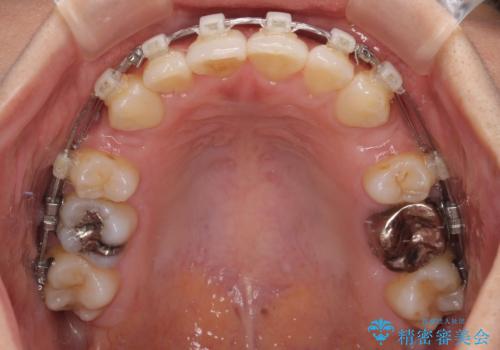

- クリアブラケット

上下左右の第一小臼歯4本を抜歯して治療を行うことがセオリーでしたが、左下は第二小臼歯が銀歯であったため、イレギュラーではありますが、そちらを抜歯しました。

その影響で治療期間は長くなりましたが、処置していない歯を保存することができました。